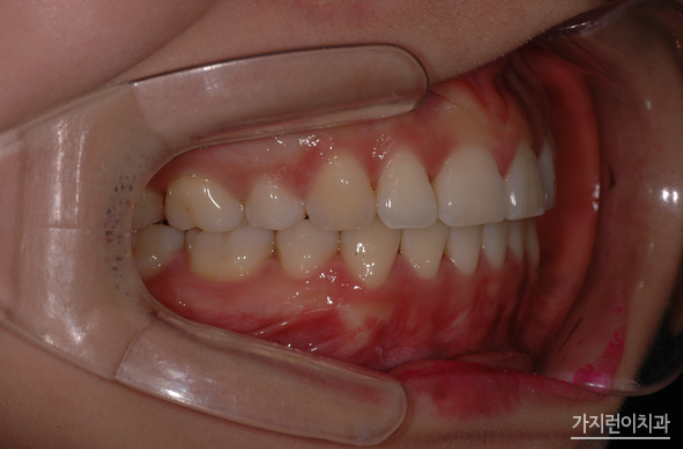

위 케이스는 돌출입 교정을 진행했지만 옥니로 변해버린 치아 케이스인데요. 돌출입 재교정은 실패 원인을 정확하게 파악하고, 해당 문제를 바로잡아야 하기에 보다 세세하게 환자 상태를 파악할 수 있는 진단 장비를 갖추고 있어야 합니다. 또한 의료진이 충분한 임상 경험을 가지고 있어야 하죠. 해당 분의 경우 돌출입 교정을 받았지만 개선 정도가 미비했으며 치열은 가지런해졌지만 과도한 교정력에 의해 하악 앞니가 옥니 형태가 되었다는 점이었습니다.

이 사진은 치료가 끝난 후 모습입니다. 다소 흐트러졌던 치열도 가지런하게 배열되었고, 무엇보다 옥니 증상이 확연히 개선된 것을 확인할 수 있었는데요. 도드라져 보이던 상악 돌출도 만족스러울 정도로 개선된 모습을 볼 수 있습니다. 사실 돌출입은 안모 변화가 큰 편이라 살펴보지 않을 수가 없는 부분인데요. 재교정 전에는 상악 돌출로 인해 입이 잘 다물어지지 않았고, 입을 다물기 위해서는 입술 아래 턱에 힘을 주어야만 했다면 이후에는 자연스럽게 입이 다물어지고, 이상적인 측면 페이스라인을 확인해볼 수 있게 되었습니다.